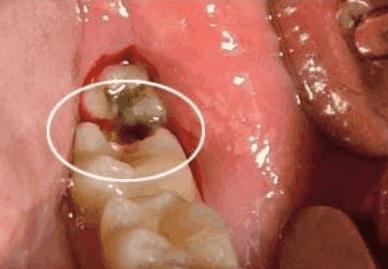

虽然我们的牙齿看起来很硬,能咬碎硬硬的东西。但是,她却很怕酸的腐蚀。所以在我们吃完食物而又不注意清洁牙齿后,牙齿就会慢慢被酸腐蚀。这样时间长了,腐蚀的范围和程度也变大。

最后在牙齿表面会出现好像有虫子咬过一样的洞,这样就成了虫牙。